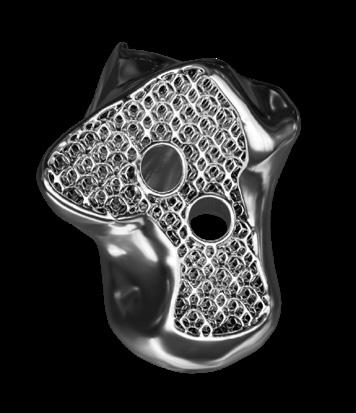

COMPONENTS

• Anatomic component design for natural load-sharing and reduced stress shielding.

• Semi-constrained fixed-bearing system built for both primary and revision ankle arthroplasty.

• Broad sizing: UHMWPE inlays in 4 thicknesses and two offsets plus full tibial/ talar size offerings.

YEARS OF CLINICAL EXCELLENCE